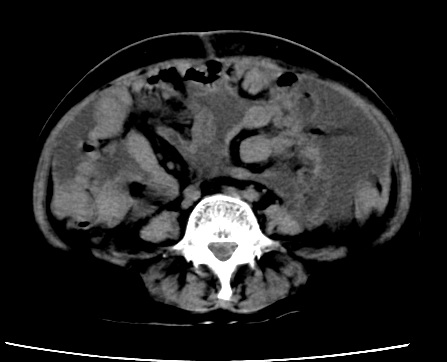

标题: CT23975:女61岁,腹部不适,明显消瘦

既往5年前卵巢癌行子宫及附件切除,右乳癌术后一年,考虑腹膜转移?

大量腹水,考虑腹膜转移。肝脏低密度灶。1囊肿,2转移。

1)结合病史,考虑腹膜及网膜转移瘤。2)肝脏多发性低密度灶,不排除转移瘤。3)大量腹水。

考虑卵巢癌行子宫术后复发,并肝、腹腔 、大网膜转移可能性大。

大量腹水。